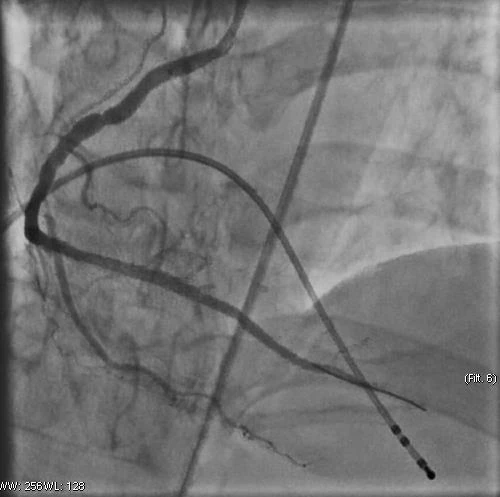

Hình ảnh Động mạch vành đã được tái thông sau khi đặt stent

Người bệnh nhanh chóng được chuyển vào phòng can thiệp tim mạch để chụp và can thiệp mạch vành tái thông mạch vành bị tắc. Kết quả cho thấy động mạch vành phải bị tắc hoàn toàn. Ekip can thiệp đã tiến hành đặt máy tạo nhịp tim cho người bệnh và đặt 1 stent vào vị trí bị tắc nhằm tái thông động mạch vành.